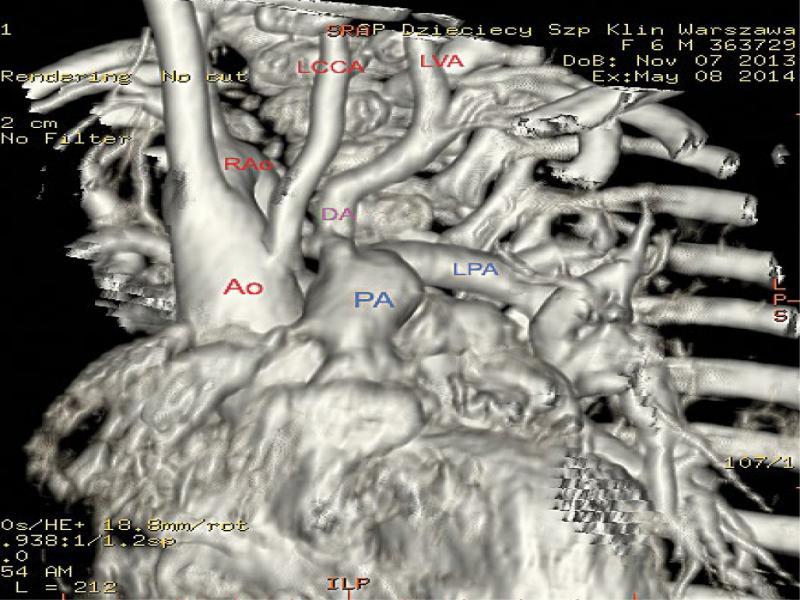

Preoperative CT angiography. Ao – ascending aorta, PA – pulmonary trunk, LPA – left pulmonary artery, RAo – right aortic arch, DA – ductus arteriosus, LCCA – left common carotid artery, LVA – left vertebral artery

The diagnosis was extended by CT angiography (Fig. 9) – the presence of isolated left subclavian artery giving rise to a tortuous patent ductus arteriosus extending vertically (from the anterior aspect) to the pulmonary trunk was confirmed. It was shown that the major portion of left vertebral flow is directed to the ductus arteriosus and pulmonary circulation. We assumed that closure of the ductus arteriosus will reduce steal from the left vertebral artery, which supplies both the ductus and the normal left subclavian artery; therefore, it will not increase cerebral circulation disorders or reduce blood supply in the left upper extremity(10,11).